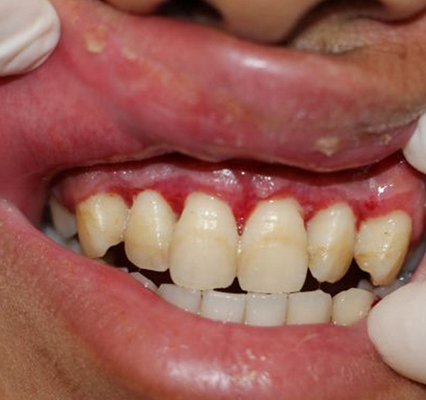

牙齦炎圖片

牙齦炎和牙周炎